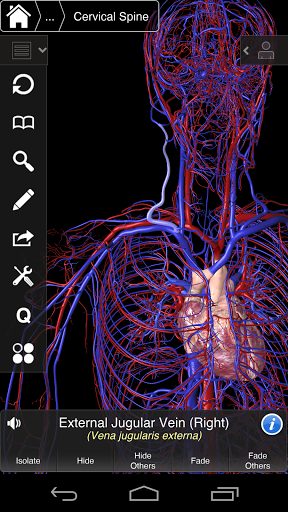

Essential Anatomy 3 represents the latest in groundbreaking 3D technology and innovative design. A cutting edge 3D graphics engine, custom built by 3D4Medical from the ground up, powers a highly-detailed anatomical model and delivers outstanding quality graphics that no other competitor can achieve.

The app represents a unique approach to learning general anatomy. The graphics are unparalleled and make learning, through the use of informative content and innovative features, a rich and engaging experience.

⁃Veins

⁃Arteries

Essential Anatomy 3 is responsive, visually stunning and effortless. The app is fully 3D, meaning that you can view any anatomic structure in isolation, as well as from any angle.

---- Over 4,000 highly detailed anatomical structures

---- Latin nomenclature for each anatomical structure